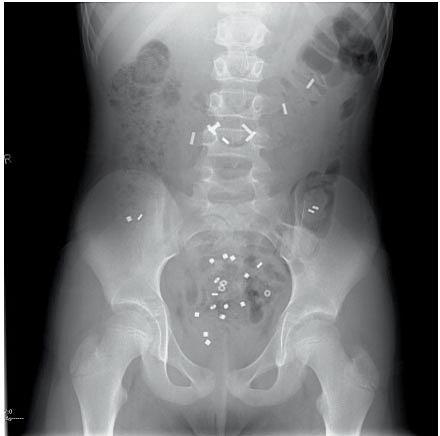

Udredning for funktionel obstipation foregår primært hos den praktiserende læge efter Dansk Pædiatrisk Selskabs retningslinjer [6]. Oftest er grundig anamnese og objektiv undersøgelse nok til at stille diagnosen funktionel obstipation. Dette kan suppleres med en afføringsdagbog ført over en 2-3-ugers periode. Organisk årsag skal udelukkes; den hyppigste er mb. Hirschsprung. Ved behandlingsrefraktær obstipation kan der være behov for henvisning til en specialafdeling. Transabdominal ultralydskanning af rectumdiameteren er en noninvasiv, hurtig og for barnet og forældrene illustrativ undersøgelse. Undersøgelsen bruges som led i udredning og i opfølgning. Colontransittidsbestemmelse bruges primært i dag til differentiering mellem fækal inkontinens med og uden obstipation. Det er vigtigt at stille diagnosen så tidligt som muligt, da en hurtigt igangsat behandling vil bedre effekten betydeligt. Den hyppigst anvendte behandling af obstipation består af de fire elementer: undervisning, udtømning, vedligeholdelsesbehandling og opfølgning. Undervisningen har to formål: at give familien og barnet en forståelse for tilstanden og at sikre barnet instruktion i gode toiletvaner. Udtømning er nødvendig inden påbegyndelse af vedligeholdelsesbehandling. Udtømning initieres oftest ved at give højdosis-polyethylenglycol (PEG) 1,0-1,5 g/kg i 3-6 dage evt. suppleret med klyx i tre dage [6]. Vedligeholdelsesbehandlingen påbegyndes i forlængelse af udtømningen. Laksantia grupperes efter, om virkningsmekanismen primært er osmotisk (laktulose, magnesiumoxid eller pulver med macrogol 3350 og elektrolytter) eller peristaltikfremmende (bisacodyl eller natriumpikosulfat). Til børn > 2 år foretrækkes PEG, hvorimod der til børn < 2 år anbefales laktulose. Peristaltikfremmende midler er ikke en del af standardbehandlingen ved funktionel obstipation. Til justering af behandling findes redskabet Bristolskalaen, som er en illustration af afføringstyper. Denne skala bruges også som led i udredningen. Et behandlingsforløb bør minimum vare seks måneder og ofte 12 måneder.